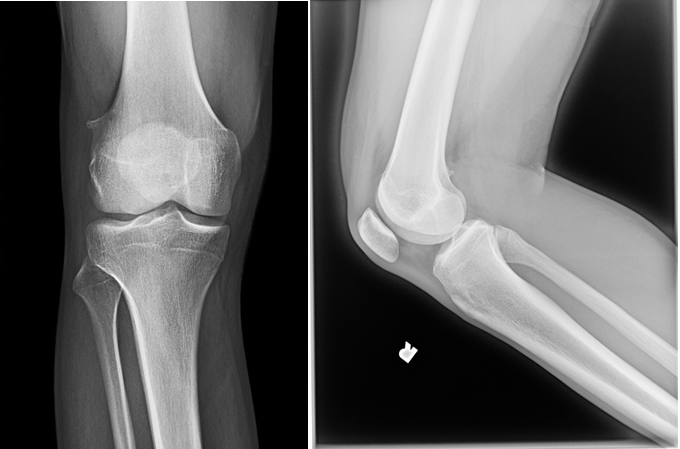

A 79-year old female presents with complaints of right hip pain for 2 months. She denies prior injury or precipitating event. The pain is made worse by lying on the affected side and occasionally hurts with hip motion. The pain is improved with NSAIDS and placing ice on the lateral aspect of her hip. Her primary care physician ordered x-rays which showed a bone lesion in the proximal femur. Her PCP was concerned she had bone cancer and ordered an MRI of the thigh to further evaluate. AP x-ray and a coronal MRI image are shown above. The patient denies a history of weight loss, fatigue, and history of cancer. On exam the patient has no pain with passive range of motion of the hip in all planes. She has pain with palpation over the greater trochanteric bursae. Motor and sensation are intact throughout the lower extremities. What is the most likely cause of this patient’s pain?